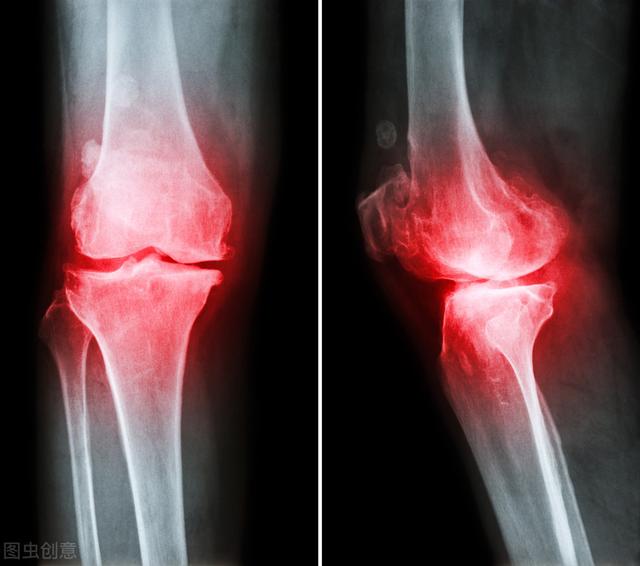

骨质增生

我们俗称的骨质增生或者骨刺,也就是医学术语里的"骨赘",常见于中老年

其实骨刺是骨质增生,骨质增生并不是一种疾病,它主要是我们身体的一种